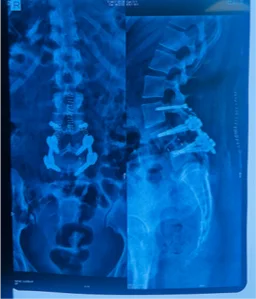

Before & After Clinical Gallery

We showcase real patient cases (with consent), including:

• Pre- and Post-operative MRIs and X-rays

• Disc Herniations, Stenosis, and Spondylolisthesis cases

• Visible improvement in alignment and decompression

Before

After